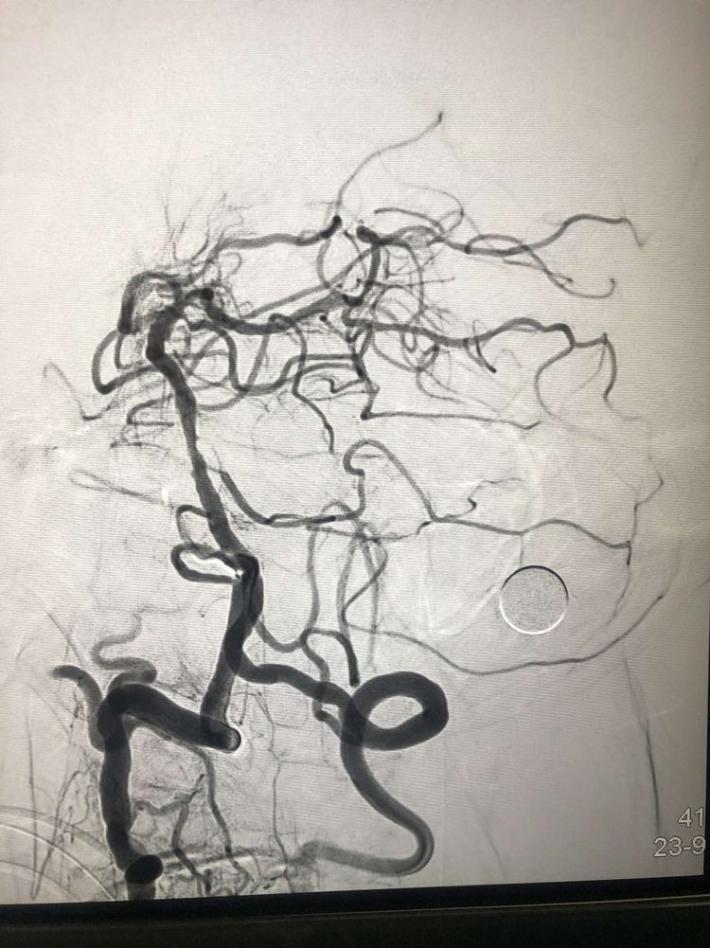

入院后75min,股动脉穿刺成功,后循环造影及右侧颈内动脉正侧位。

导丝导管通过闭塞部位,经微导管造影,证实在远端真腔内,取栓后M1重度狭窄,球囊扩张。

球囊扩张

支架植入术后前向血流通畅